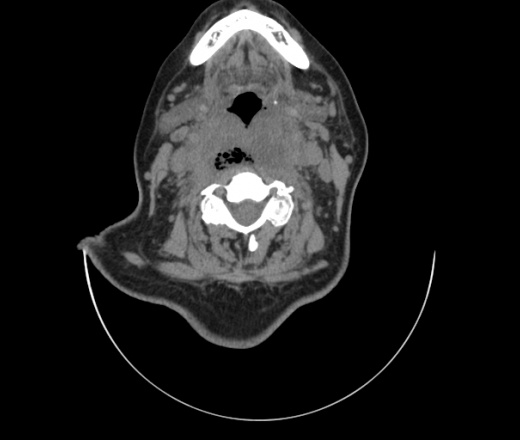

Женщина поступила в х/о спустя 4 дня после того как при употреблении карася подавилась костью.

Наличие газа в средостении на протяжении тел С2-С6 (медиастинальна эмфизема); рыбная кость на уровне тела С6.

При всем уважении, но говорить о медиастинальной эмфиземе, оценивая мягкие ткани шеи, как-то слишком резко. На мой взгляд, это ретрофарингеальное пространство.

Эвакуировали почти 100мл гноя. Но кость не смогли найти. Думаю что она даст дальнейшее ослоднение. Эндоскопически за черпалонадгортаной звязкой не смогли зайти в пищевод, все мягкие ткани отечные, просвет пищевода сдавлен. По всей видимости параэзофагеальная клетчака тоже задействована. Эмпиема, если ее можно так назвать, незнаю как правильно дошла до уровня яремной вырезки. Чем закончиться напишу. Ждем медиастинита.

Флегмона заглоточного пространства шеи, только операция, флегмоны вскрывают. Риск медиастинита.

Согласен с Вами; конечно, наличие газа в клетчатке ретрофарингеального пространства (затмение с опечаткой..). К сожалению, процесс "продвигается" к медиастиниту. Но почему никто, не отмечает наличие рыб. кости; или это для Всех очевидно?

Так вы уже отметили. Хотя ориентировал бы не скелетотопически, а на перстнечерпаловидный сустав.

Кость то мы сразу выявили, размеры где то 17*2мм, но ее так и не получается найти в этой каше